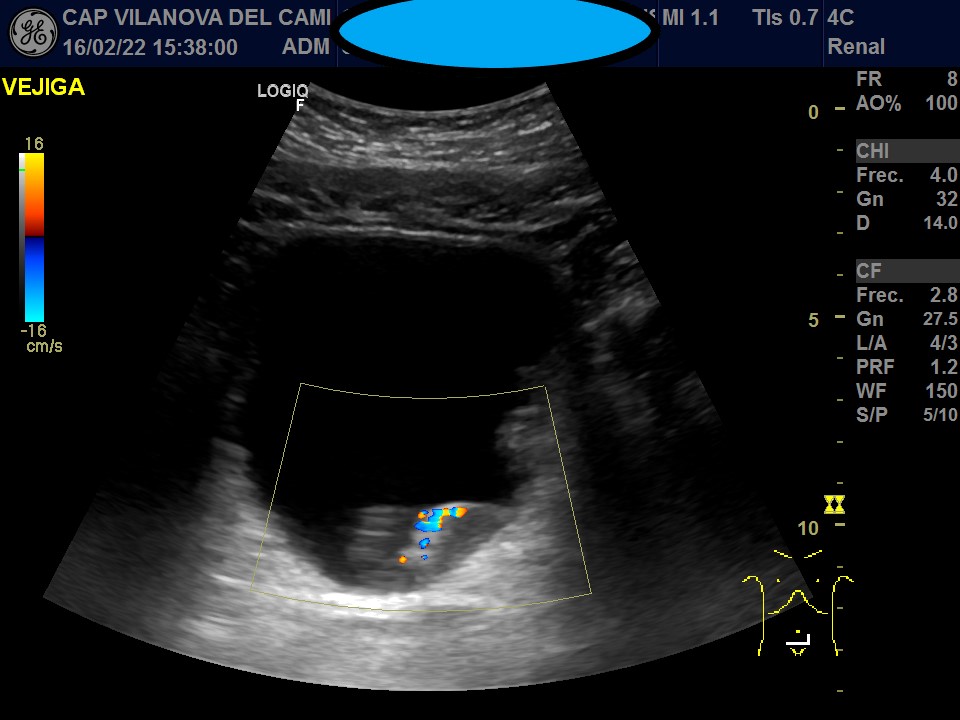

Vejiga urinaria bien distendida, de paredes engrosadas, con imágenes sugestivas de patología intraluminal y parietal. Neoformación irregular en pared posterolateral izquierda y suelo pélvico, que respeta el trígono vesical y la salida del meato ureteral, con captación Doppler color y algunas imágenes hiperecogénicas sugestivas de calcificación en su interior.